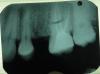

Book Опубликовано 6 июня, 2011 Поделиться Опубликовано 6 июня, 2011 Добрый день. Помогите, пожалуйста. Сильные боли в правой верхней челюсти. Врачи говорят, что все в порядке. На снимках ничего им не видно. Я думаю, что болит 16, но точно сказать не могу. Боли усиливаются к ночи, днем ноет, но терпимо. 16 вскрывали, прочистили каналы, поставили пломбу, боли не прошли. Меня направили к эндодонтисту, чтобы еще раз прочистил все каналы, это стоит дорого и я не знаю, поможет ли это лечение. Мой стоматолог сказал, если эндодонтист не поможет, тогда на резекцию верхушки корня. Скажите, пожалуйста, что вы видите на снимке. Могут ли быть боли от 7-ки? Стоит ли идти к эндодонтисту или лучше удалить зуб и поставить имплантат. Не знаю уже к кому обратиться. Спасибо.P.S. Прилагаю снимки, не знаю, на каком лучше видно. Ссылка на комментарий

Book Опубликовано 6 июня, 2011 Автор Поделиться Опубликовано 6 июня, 2011 Похоже на невралгию II ветви тройничного нерва...Конечно терапевты могут сказать еще о 4 канале в 6 зубе... В общем нужна полноценная диагностика чтобы избавиться от проблемы. Т.е проблема может быть не в зубах... Вы из какого города? Скажите, пожалуйста, а 4 канал судя по снимку не найден и не прочищен? правильно я понимаю, потому что стоматолог, который чистил каналы, сказал, что все нашел, а эндодонтист говорит, что 4 ый не найден, я не знаю, стоит ли соглашаться на поиски четвертого, вдруг не поможет. Я живу в Германии Ссылка на комментарий

Aldo Rain Опубликовано 6 июня, 2011 Поделиться Опубликовано 6 июня, 2011 4 канала может и не быть, на дентальной компьютерной томографии его можно было бы лицезреть я думаю. А что было с 5 зубом, почему удалили? И почему депульпировали 6? Какие были жалобы, опишите подробнее немного Ссылка на комментарий